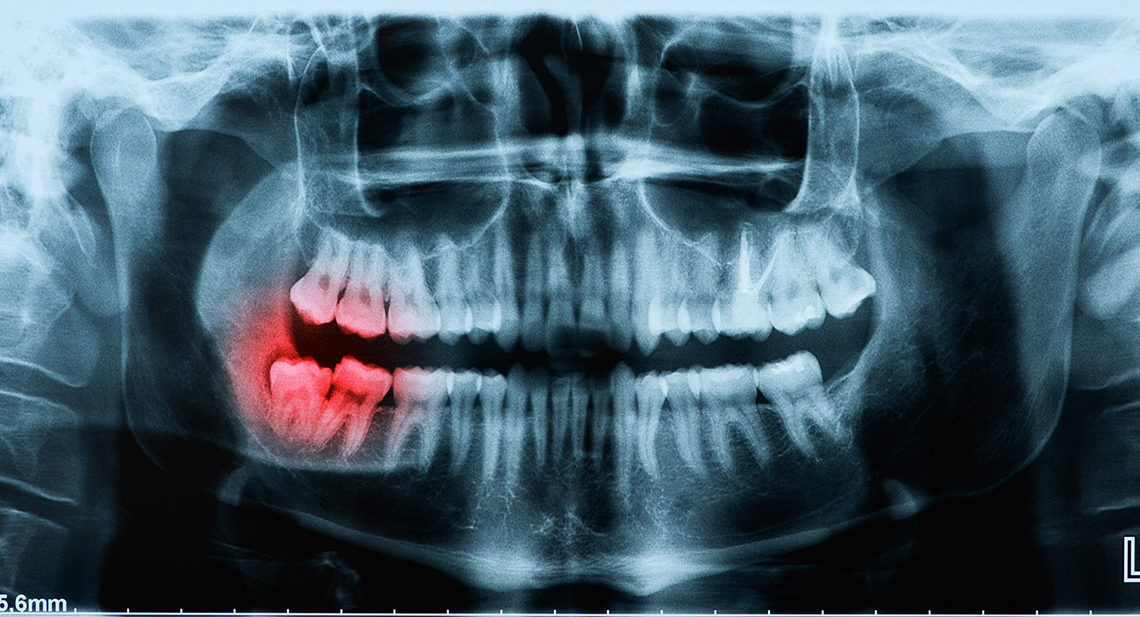

Tooth Contouring Can Reshape Your Teeth

How Dental Contouring Works

When a skilled and trained cosmetic dentist uses the technique, tooth contouring can be performed with little to no patient discomfort. Before having the procedure, dental x-rays will be taken to evaluate the size and location of the pulp of each tooth to ensure that there is enough bone between the teeth to provide proper support. Your dentist will then gently start to remove a small amount of tooth enamel with a laser or drill. Your provider will trim any misshapen areas, excessively long teeth will be shortened, and poorly shaped teeth will be evened out for proper bite and alignment. After the contouring is complete, your dentist will polish your teeth for a natural-looking shine. Depending on the extent of the contouring recommended, reshaping may take just one 30 minute appointment to transform your teeth.

Broken Wisdom Tooth – Is It Considered An Emergency?

Wisdom teeth are usually the last adult teeth to come through and tend to erupt in the later teens or early twenties. Known as the third molars, they do not always come through the gums at all, and if they do, sometimes they may not be straight.

In these cases, there may be an increased risk of infection. Gaps allow debris to gather and bacteria to grow, which raises the risk of gum disease and tooth decay. Some experts recommend the early removal of wisdom teeth to avoid such occurrences, while others believe it is best to leave them alone if possible.

However, one situation where your dentist is very likely to recommend removal is if a wisdom tooth is broken. While it is possible to retain the broken tooth, to avoid further complications, it is best to get the tooth removed completely.

Why Do Wisdom Teeth Break?

As wisdom teeth are the last to come through, there may be limited space in your mouth. As they try to erupt through your gum, another tooth may already be occupying the same spot. Your wisdom tooth may come through at an unnatural angle, or even crack as it forces its way out.

Wisdom teeth may be more likely to break than your other teeth if they have not erupted correctly. You may find it more challenging to use those teeth to chew, and there is a greater chance of decay if it is harder to clean thoroughly around that area.

As with any other tooth, your wisdom teeth are susceptible to blunt force trauma, such as an impact on your jaw, or biting into something hard. If your teeth crack, or fragments of your wisdom tooth break off, this is likely to cause discomfort.

Risks from Having a Broken Wisdom Tooth

Bacteria can thrive in gaps where bits of the tooth broke. A gap in a wisdom tooth is a hospitable environment for an infection and a weak point in the tooth.

Additionally, a broken or cracked wisdom tooth puts the entire tooth’s health at risk. Bacteria can invade the tooth and infect the dental pulp. In those cases, the tooth must either be extracted or given a root canal treatment. In most cases, it’s better just to remove the tooth.

It is essential to see your dentist quickly if you have a broken wisdom tooth. Your dentist will carry out an assessment and tell you if you should have a wisdom tooth extraction.

Although it is possible to fill a broken tooth, or repair it using a crown, you will want to consider removing your wisdom tooth. Wisdom teeth usually do not bring any real benefits to your mouth, but they can increase the chances of breakages and infections.

Wisdom Teeth Removal

If you need to have your wisdom teeth removed, your dentist can perform the procedure in just one visit. Depending on how your tooth has erupted through the gums and sits in the jawbone, you may need a simple or complex extraction.

In a simple extraction, your dentist numbs the area around the tooth and using a rocking motion, loosens the tooth from its socket. In a complex extraction, you may require general anesthesia or conscious sedation, especially if you are an anxious patient.

Your dentist makes an incision in the gum line and breaks the tooth into sections, removing the pieces. After the extraction, your dentist places a piece of gauze over the site to stem the bleeding and may use sutures. Bring a chaperon to drive you home, as the sedation’s effects can last in the body for a few hours after your procedure.